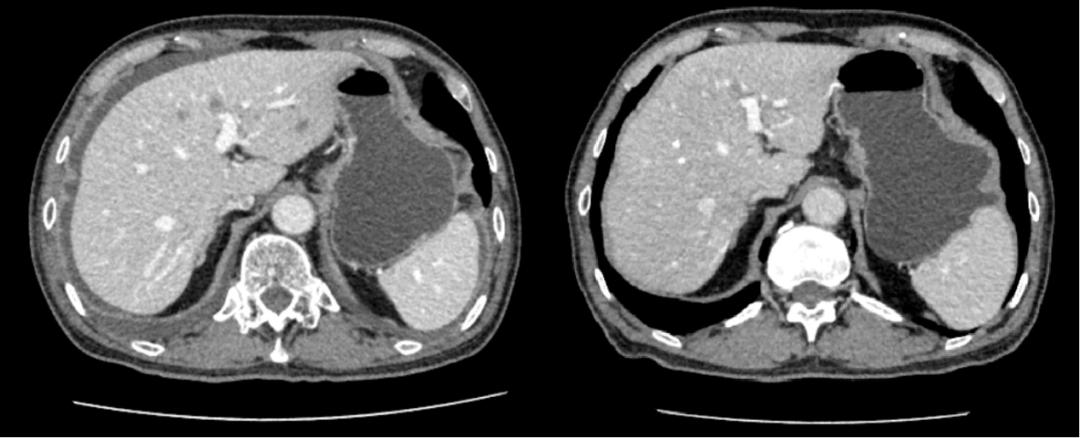

翟大爷进行化疗后,肝脏转移灶明显缩小减少,腹水消失

给翟大爷的化疗方案结合了靶向药物,经过化疗,他的结肠肿瘤缩小,腹膜转移癌、转移的淋巴结明显消失,腹水消失。利用最新的超声引导下消融技术,结合以前CT检查肝脏肿物的部位,可以做到对转移瘤的位置进行精准的射频消融。

经过前一阶段的治疗,肝脏的转移癌已经几乎完全消失,超声检查下难以观察到。手术前,医生对翟大爷进行了一次超声引导下的肝脏肿物消融治疗,经过治疗,再次检查评估时,翟大爷的肝脏在CT检查上几乎看不到肿瘤。